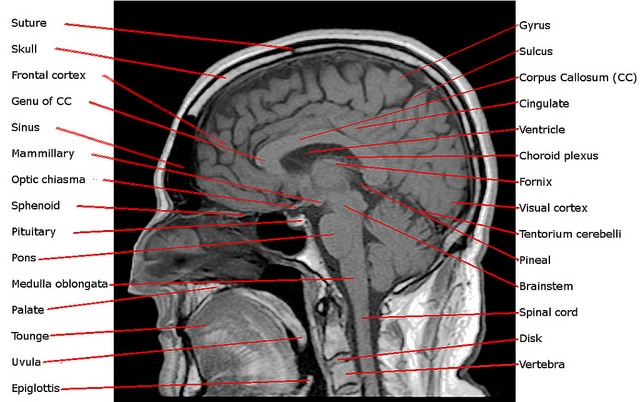

Additionally, there is a type of mri called magnetic resonance angiography (mra) , which better examines the blood vessels in the brain. Magnetic resonance imaging (mri) has given doctors the ability to obtain very good images of the brain's structures. Mri brain is a specialist investigation that is used for the assessment of a number of neurological conditions.

Magnetic resonance imaging (mri) is a test that uses powerful magnets, radio waves, and a computer to make detailed pictures of the inside of your body.

Side effects of an mri are claustrophobia and anxiety. Mri (magnetic resonance imaging) is the diagnostic tool that identifies structural changes in the brain that may cause seizures or be associated with epilepsy. Additionally, there is a type of mri called magnetic resonance angiography (mra) , which better examines the blood vessels in the brain. An overview of magnetic resonance imaging (mri), including different sequence types (t1, t2, stir, flair) and a structured approach to mri interpretation.